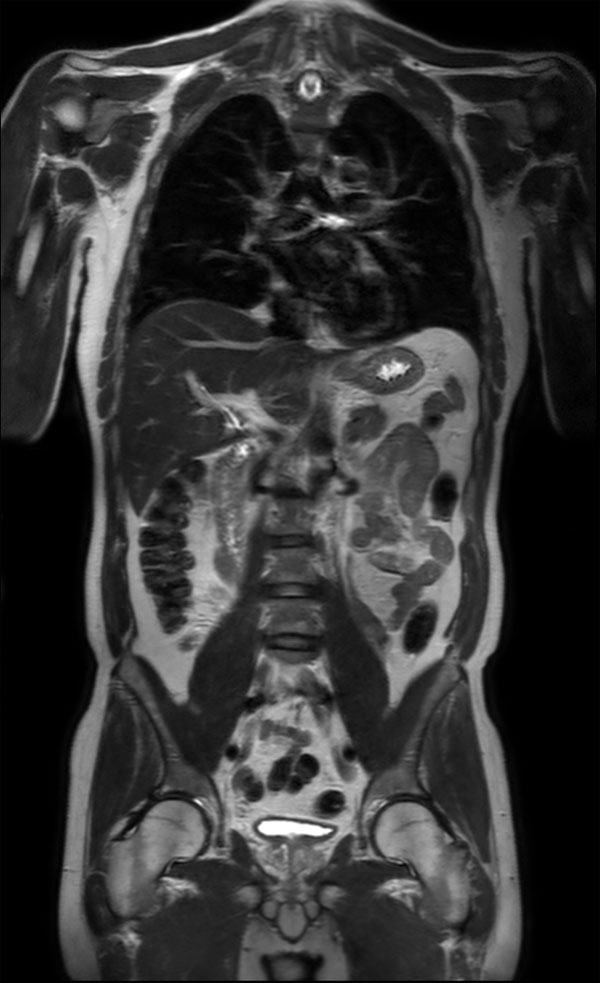

Advanced Liver MR - mDIXON Quant

University of Michigan Hospital, Ann Arbor, USA